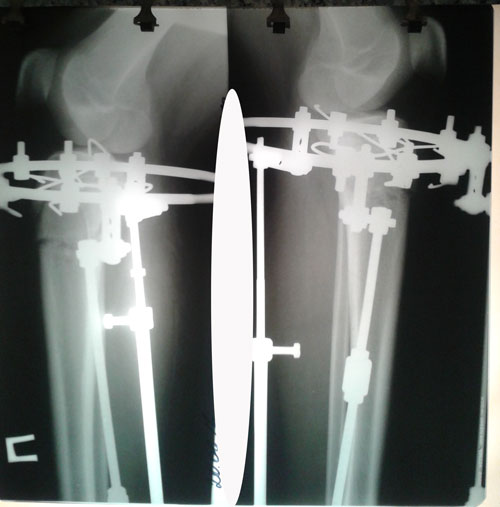

Рентген на фиксации.